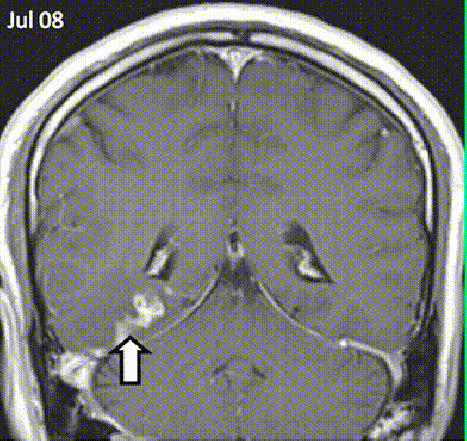

Αυτή η φωτογραφία δείχνει τα αποτελέσματα του Taenia Solium, που όπως και το Spirometra Erinaceieuropaei, κατοικεί σε μυς των γουρουνιών.